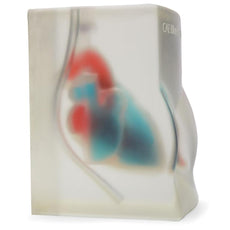

Replacement tissue insert for Central Line and Regional Anesthesia Model (BPHNB670 series).-